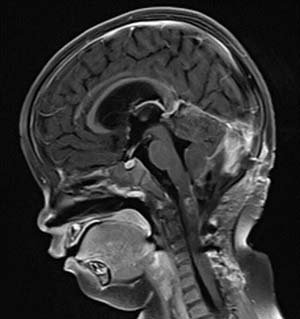

面對這一挑戰(zhàn),由我國著名神經(jīng)外科專家張玉琪教授率領(lǐng)的手術(shù)團隊為阿什利實施“枕下后正中入路腦干及頸髓病損切除術(shù)”。在四個小時的手術(shù)中,張玉琪教授精細(xì)操作,在保護周圍腦組織、神經(jīng)與血管的前提下,實現(xiàn)了腫瘤鏡下大部切除,術(shù)中出血僅100毫升。術(shù)后病理證實為毛細(xì)胞星形細(xì)胞瘤(WHO I級)。

術(shù)后影像(MRI)

然而術(shù)后恢復(fù)之路仍充滿波折。因并發(fā)腦積水,患兒出現(xiàn)嘔吐等癥狀,經(jīng)脫水治療效果不佳。醫(yī)療團隊與家屬充分溝通后,再次為阿什利施行腦室-腹腔分流術(shù),術(shù)后腦積水顯著改善。與此同時,醫(yī)院為她制定并實施了系統(tǒng)化療方案,歷經(jīng)5個周期的藥物調(diào)整與精心治療,至今年7月MRI復(fù)查顯示術(shù)區(qū)強化灶已完全消失。